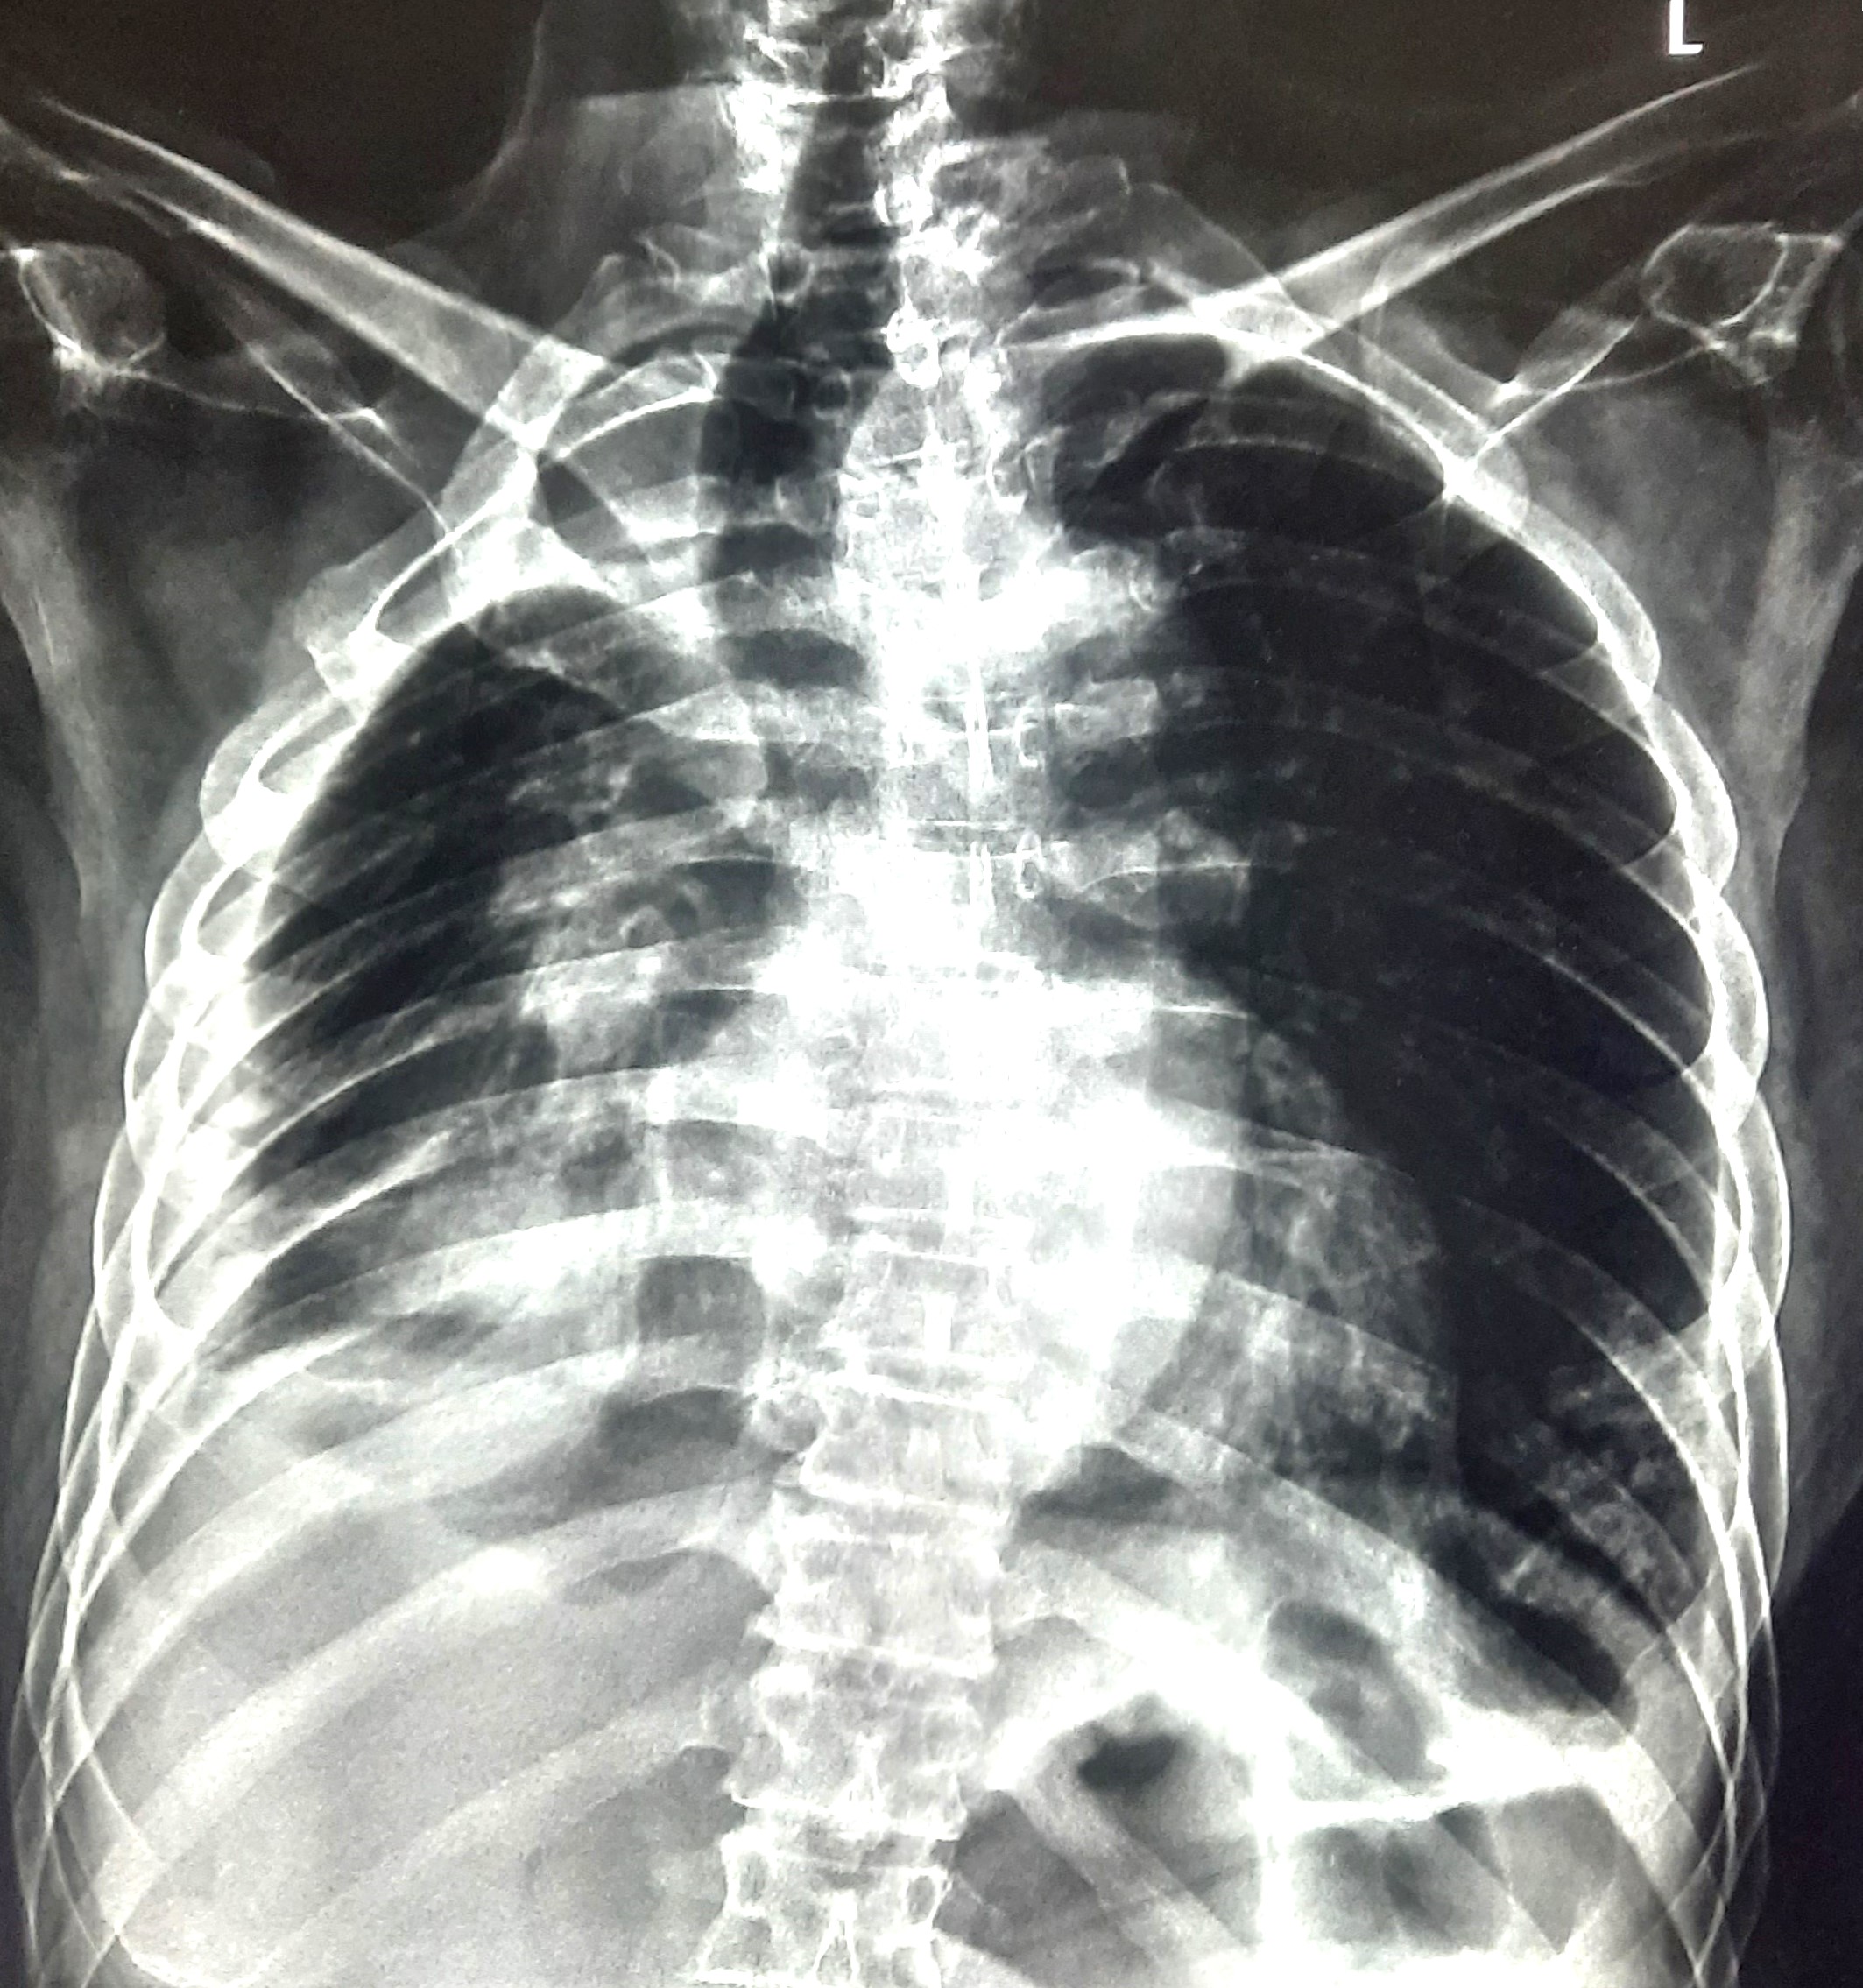

| 84 | IGGMC, Nagpur, Nagpur | P2 | 29-4388 | Dipak Panchbudhe | Consent taken on Paper | 33 Yrs. |

Provisional Diag : Pulmonary Tuberculosis Reactivation ?

Final Diag : Pulmonary Tuberculosis |

TB Case (Confirmed) | Bilateral multiple ill-defined alveolar opacity present, Left Sided Upper Zone Fibro Cavitary Lesion Present | Abnormality visible on x-ray |